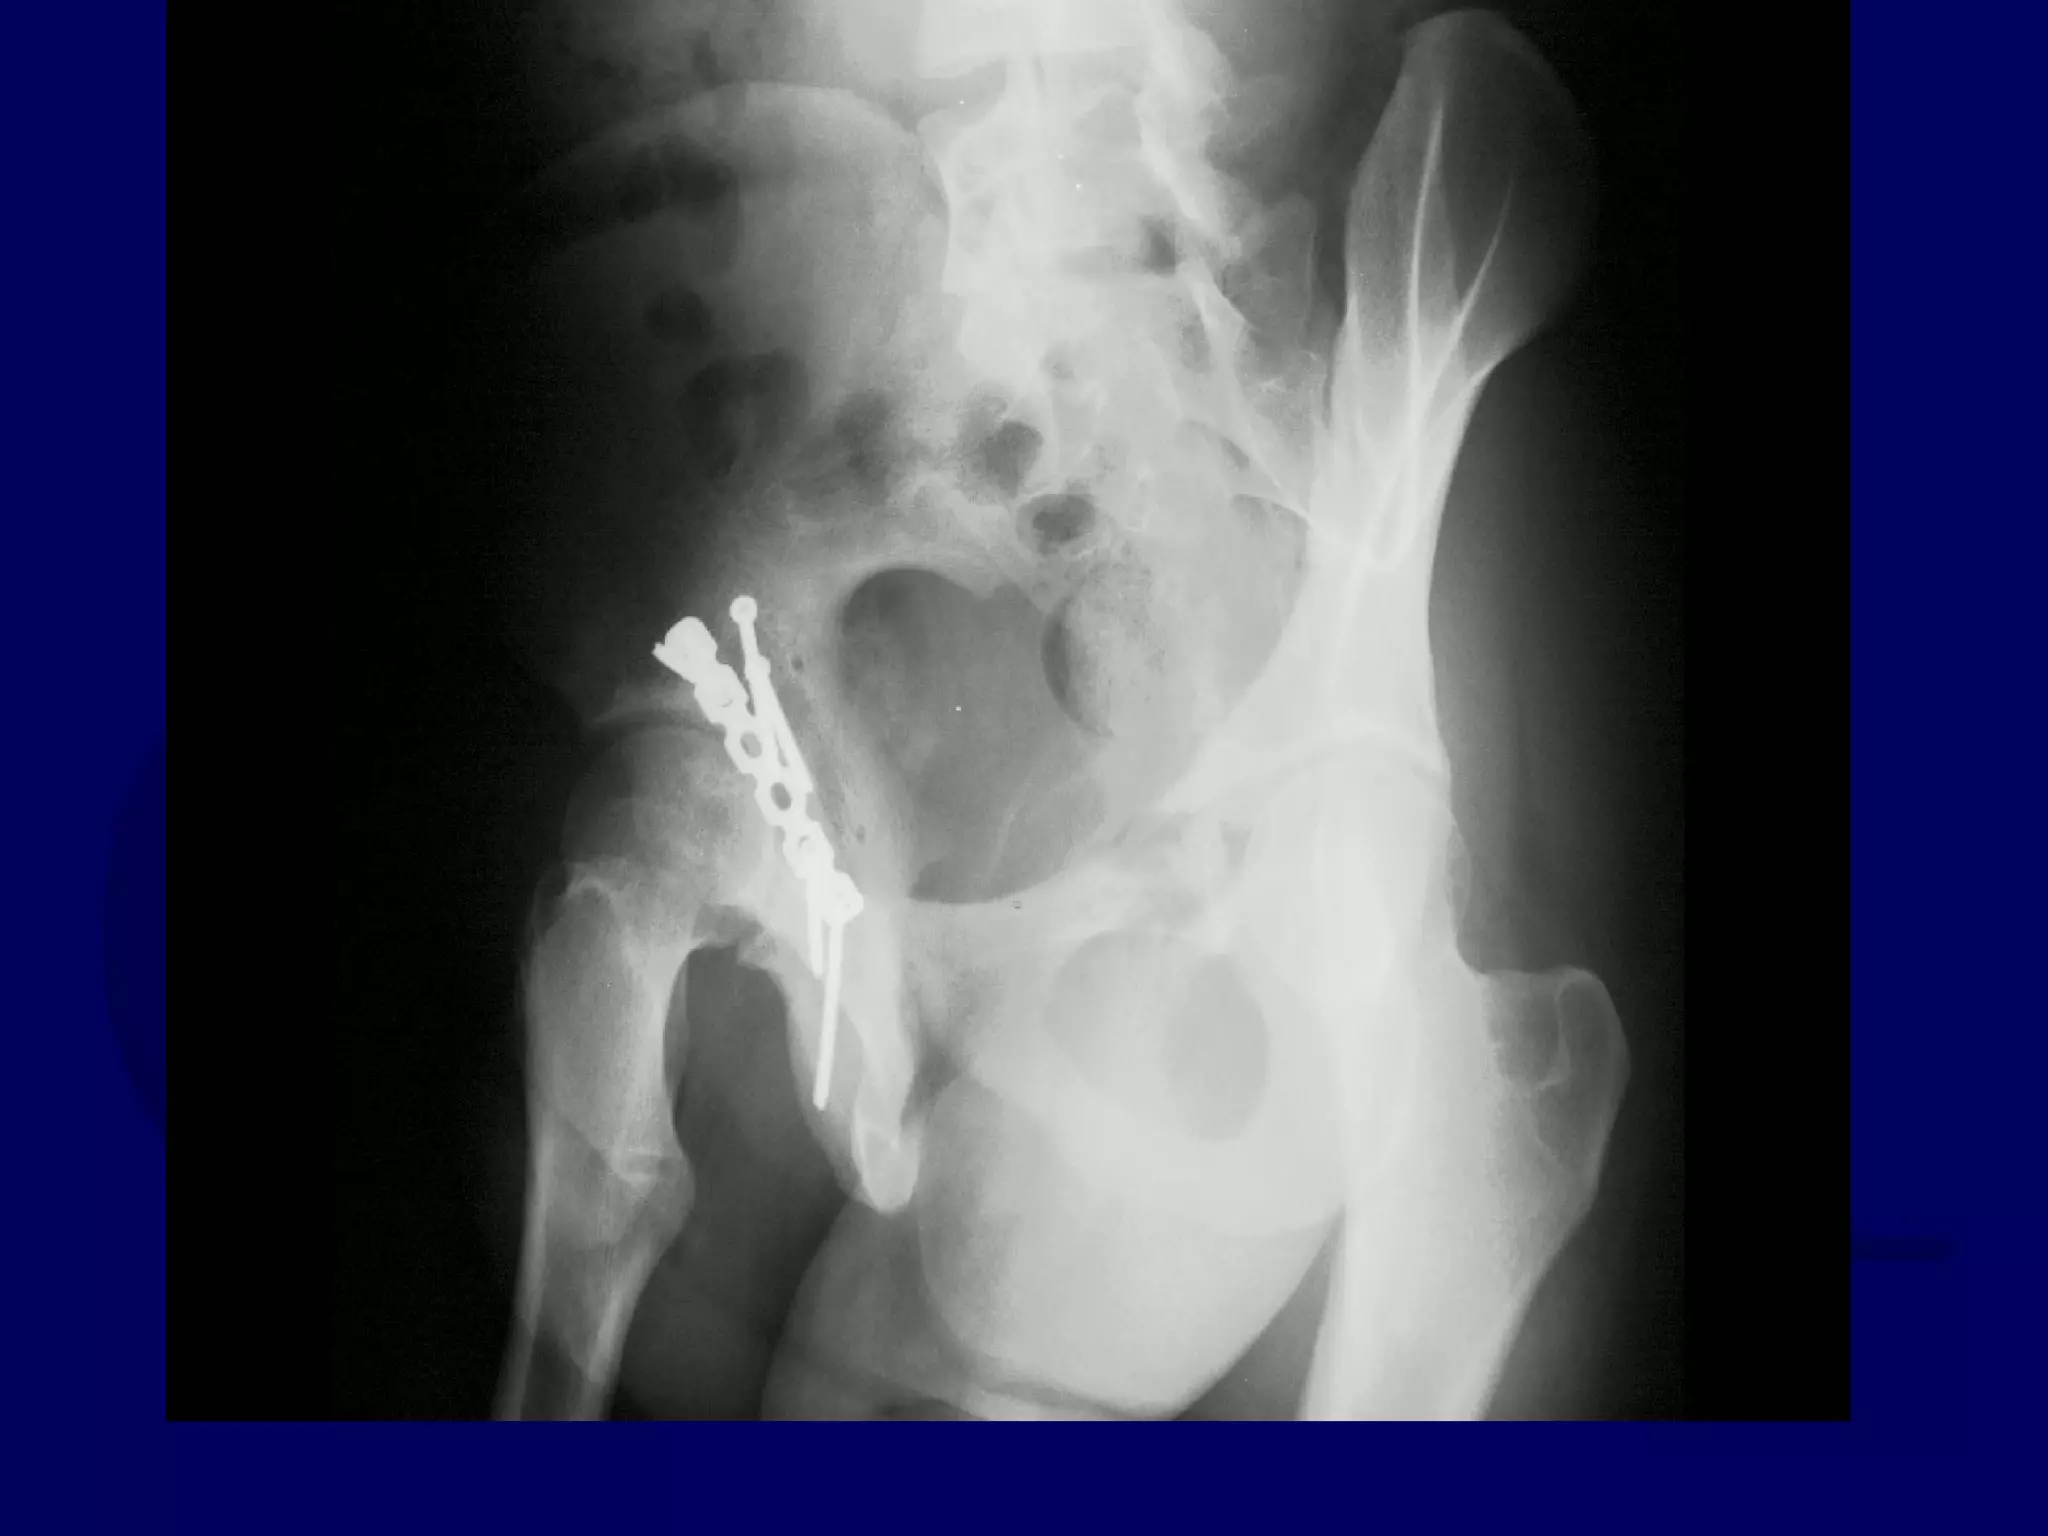

Subsequent Ilioinguinal

Approach

P.J. 00.12.22